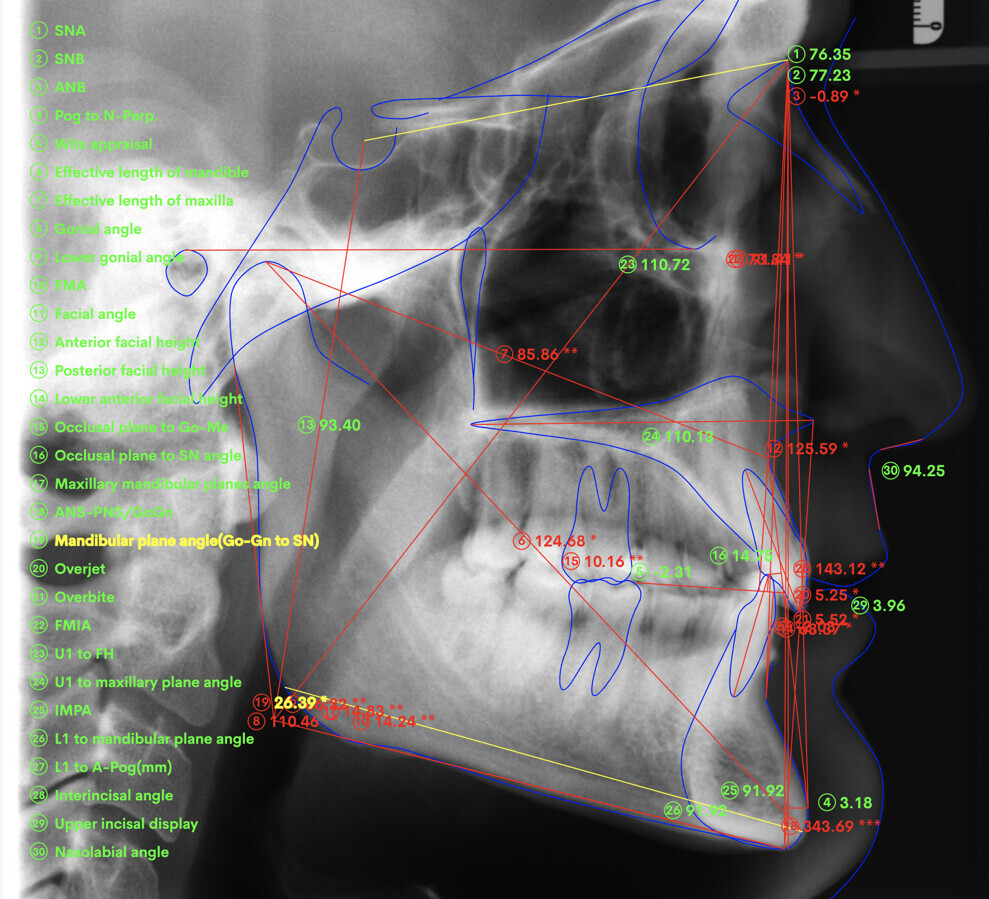

A 37-year-old male patient presented with the chief need for re establishing anterior alignment in both arches. Facial analysis showed a short face with a flat profile but proper chin projection (Figs. 9–12), and clinical examination revealed a skeletal Class I (ANB = 0.89°) and dental Class I malocclusion with severe deep bite (almost 100%), a deep curve of Spee, normal maxillary central incisor torque (Ui–FH = 110°), mild maxillary crowding and moderate mandibular crowding (Figs. 13–18). The deep bite components were represented in this patient by the severe skeletal condition of hypo divergent pattern (FMA = 14.24°) with normal maxillary and mandibular incisor inclination and decreased gonial angle (110.46°). Analysis of the cephalometric radiograph indicated a reduced lower anterior facial height, combined with a hypo-divergent pattern (Fig. 19). The only treatment option suggested was orthodontic treatment with aligners for deep bite correction with all the features described (bite ramps, pressure area, 3D curve of Spee levelling, Class II elastics and heavy occlusal contacts).

Fig. 19